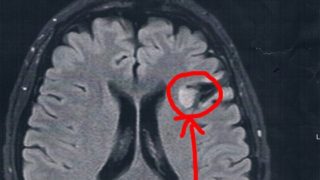

GLIOMA:手術後39ヶ月目の検査

半年ごとの定期検査のために久しぶりに病院に戻った。2014/6/23の覚醒手術から約39か月になる。MRI検査の結果、半年前や一年前と比べても変化は無し!今回2017/9/7(手術後39か月)のMRI画像前回2017/3/9(手術後33ヶ月...